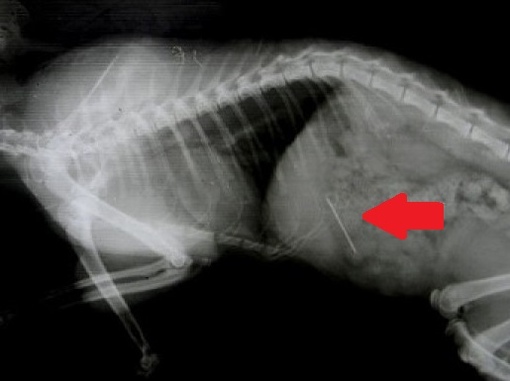

- Рентгенография – позволяет рассмотреть петли тонкого кишечника, располагающиеся в центральной зоне брюшной полости в двух проекциях – вентродорсальная и боковая. Аномальное расширение исследуемого материала сигнализирует о растяжении от постороннего предмета или от иных причин. На снимке можно обнаружить металлические вещи, кости, камни, стекло. Впрочем, не всегда инородные тела видны с помощью рентгенографии. Так, сложно обнаружить на снимке нитки, резиновые изделия, полиэтилен или тряпку. В этом случае применяют контрастную рентгенографию или другие способы исследования.

- УЗИ – еще один способ обнаружения инородных тел. Позволяет выявить наличие непроходимости по механическим причинам. Если есть инородный предмет, и двигательные функции кишечника сохранены, организм собаки будет пытаться его вытолкнуть.

Аппарат УЗИ дает возможность зафиксировать маятникообразное перемещение посторонней вещи по кишке.